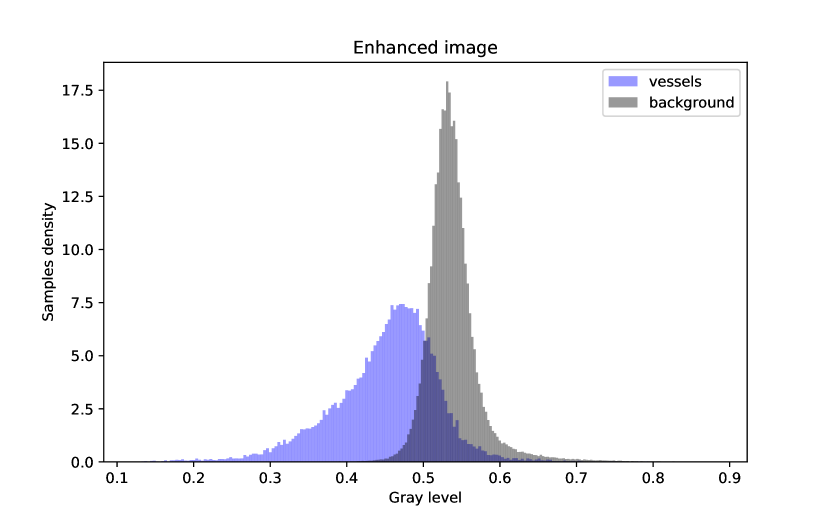

In Figure 4, an example of a retinography before and after applying the preprocessing method is provided, along with the density histograms of vessel pixels and background pixels for each image. The histograms have been computed from the images converted to grayscale.

It can be seen at first glance that the enhanced image, i.e. the one that has been preprocessed, has a greater contrast between the vessels and the background and it presents a more uniform illumination. This enhancement can also be seen in the histograms of the images.